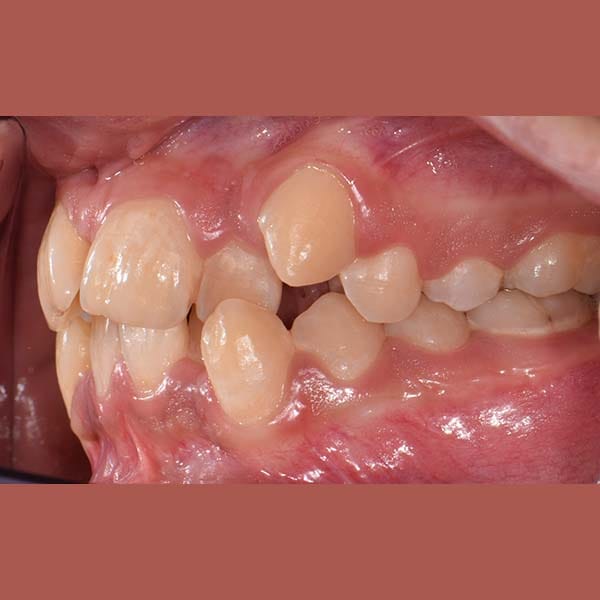

BEFORE

راجعتني والدة هذه الآنسة الشابة طالبةً أي حل لتحسين ابتسامة ابنتها، مع شرط أساسي وهو عدم قلع أي من أسنانها الدائمة.

بعد شرح أن قلع الأسنان يكون ضرورياً أحياناً، وبعد الفحص الدقيق، طمأن الدكتور خالد الكاتب الأم بأنه لحسن الحظ، حالة ابنتها تسمح بالعلاج دون قلع. اعتمدت الخطة على توسيع الفكين لفتح مسافة كافية لرصف الأسنان. تم اختيار تقويم الدايمون (ذاتي الربط) لهذه المهمة، حيث يعتبر مثالياً لهذا النوع من المعالجات التي تتطلب توسيعاً فعالاً.

كما تظهر الصور، نجحت الخطة العلاجية في رصف الأسنان بشكل ممتاز وتحقيق ابتسامة جميلة ومتناسقة. وكالعادة، أصبح بإمكان صديقتنا الشابة أن تبتسم لوالدتها ولكل من حولها بثقة وسعادة.